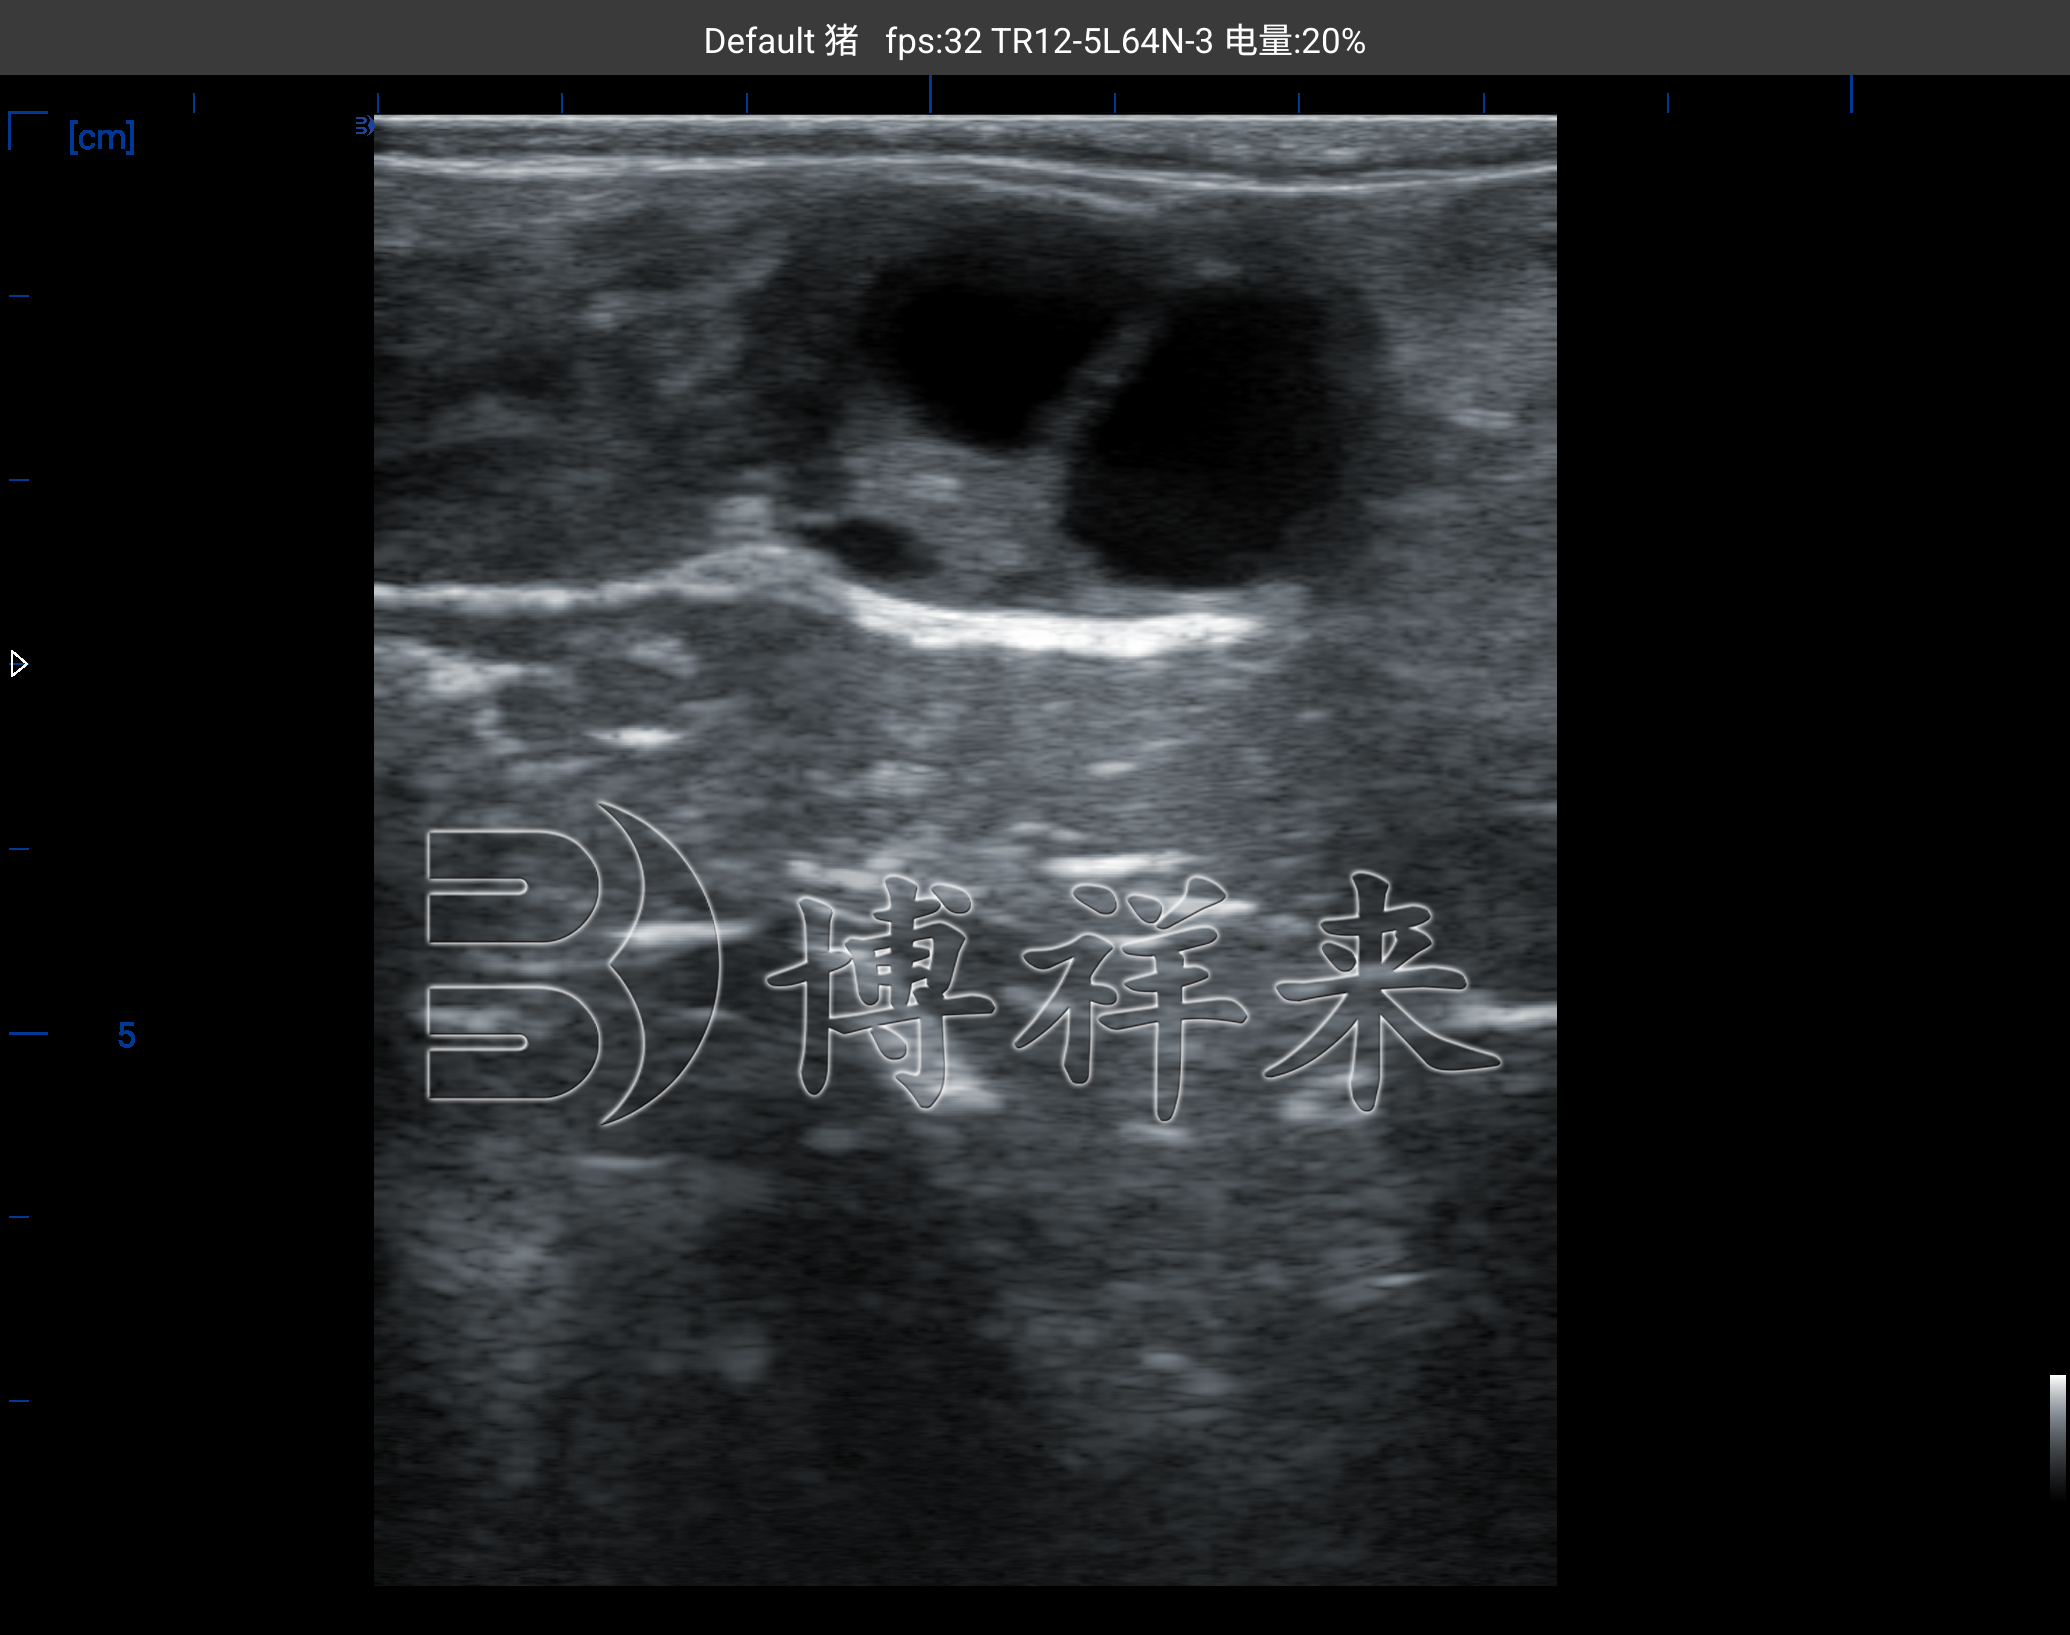

奶牛的发情表现差异大,高产牛“静立不明显”更是让基层技术人员难以准确判断发情阶段。卵泡虽然在体内,但在牛用B超机的影像下,它以一个“圆形或椭圆低回声结构”的形态呈现出来,直径、壁厚、排列方式都可以直接观察。

在卵巢表面出现大小不一的泡状结构时,通常意味着奶牛处于卵泡波的发育周期。优势卵泡一般回声均匀、轮廓清晰,而退化卵泡则呈现不规则轮廓、回声不均。接近排卵的卵泡会出现壁变薄、张力明显增强的影像特点。熟练的技术人员可以通过图像观察推断是否进入排卵前 12 小时左右的关键时期。